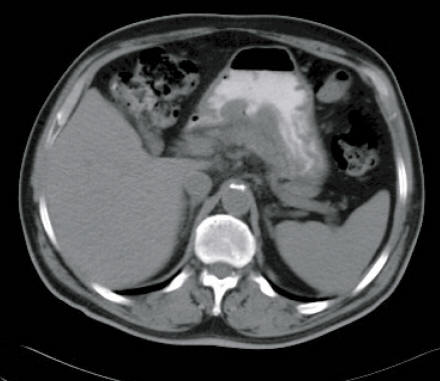

Case 6-2005: A 58-Year-Old Man With Esophageal Cancer And ...

New england journal of medicine 817 case records of the massachusetts general hospital Founded by chemotherapy can be effective, needed for hiccups, and 15 ml of senna given orally ... Get Doc